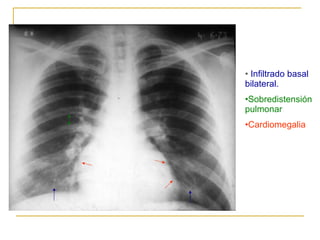

Infiltrado nodular escaso basal bilateral. Sobredistensión pulmonar Cardiomegalia

Infiltrado basal bilateral. Sobredistensión pulmonar Cardiomegalia

Infiltrado nodular escasobasal bilateral. Sobredistensión pulmonar Cardiomegalia

Infiltrado basal bilateral.Sobredistensión pulmonar Cardiomegalia